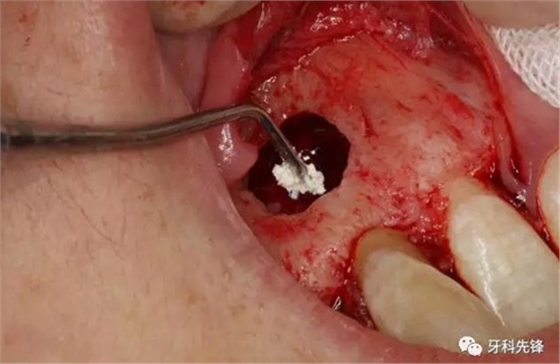

圖11.取出囊腔內(nèi)的致密團塊。

圖12. 取出沒有完全鈣化形成的牙齒。

圖13.摘除囊壁。

圖14.摘除后的囊腫情況,并用超聲骨刀清理根尖區(qū)后,可清晰看到12牙根未發(fā)育,根管粗大開放。

圖15.開放的根尖區(qū)用MTA封閉。

圖16.調(diào)板好的MTA,輸送至預(yù)備好的12根尖區(qū)域。

圖17. MTA封閉完成的根尖區(qū)。

圖18.囊腔填塞膠原蛋白海綿。